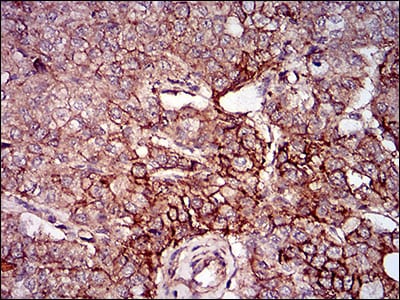

分类: 科研抗体货号: 30601别名: AMPKG应用: IHC反应种属: Human

分类: 科研抗体货号: 30598别名: AMPKG应用: IHC,IF,FCM反应种属: Human

分类: 科研抗体货号: 30597别名: NRF2应用: IHC反应种属: Human

分类: 科研抗体货号: 30596别名:应用: WB,IHC,FCM反应种属: Human

分类: 科研抗体货号: 30622别名: GDF8; MSLHP应用: IHC反应种属: Human